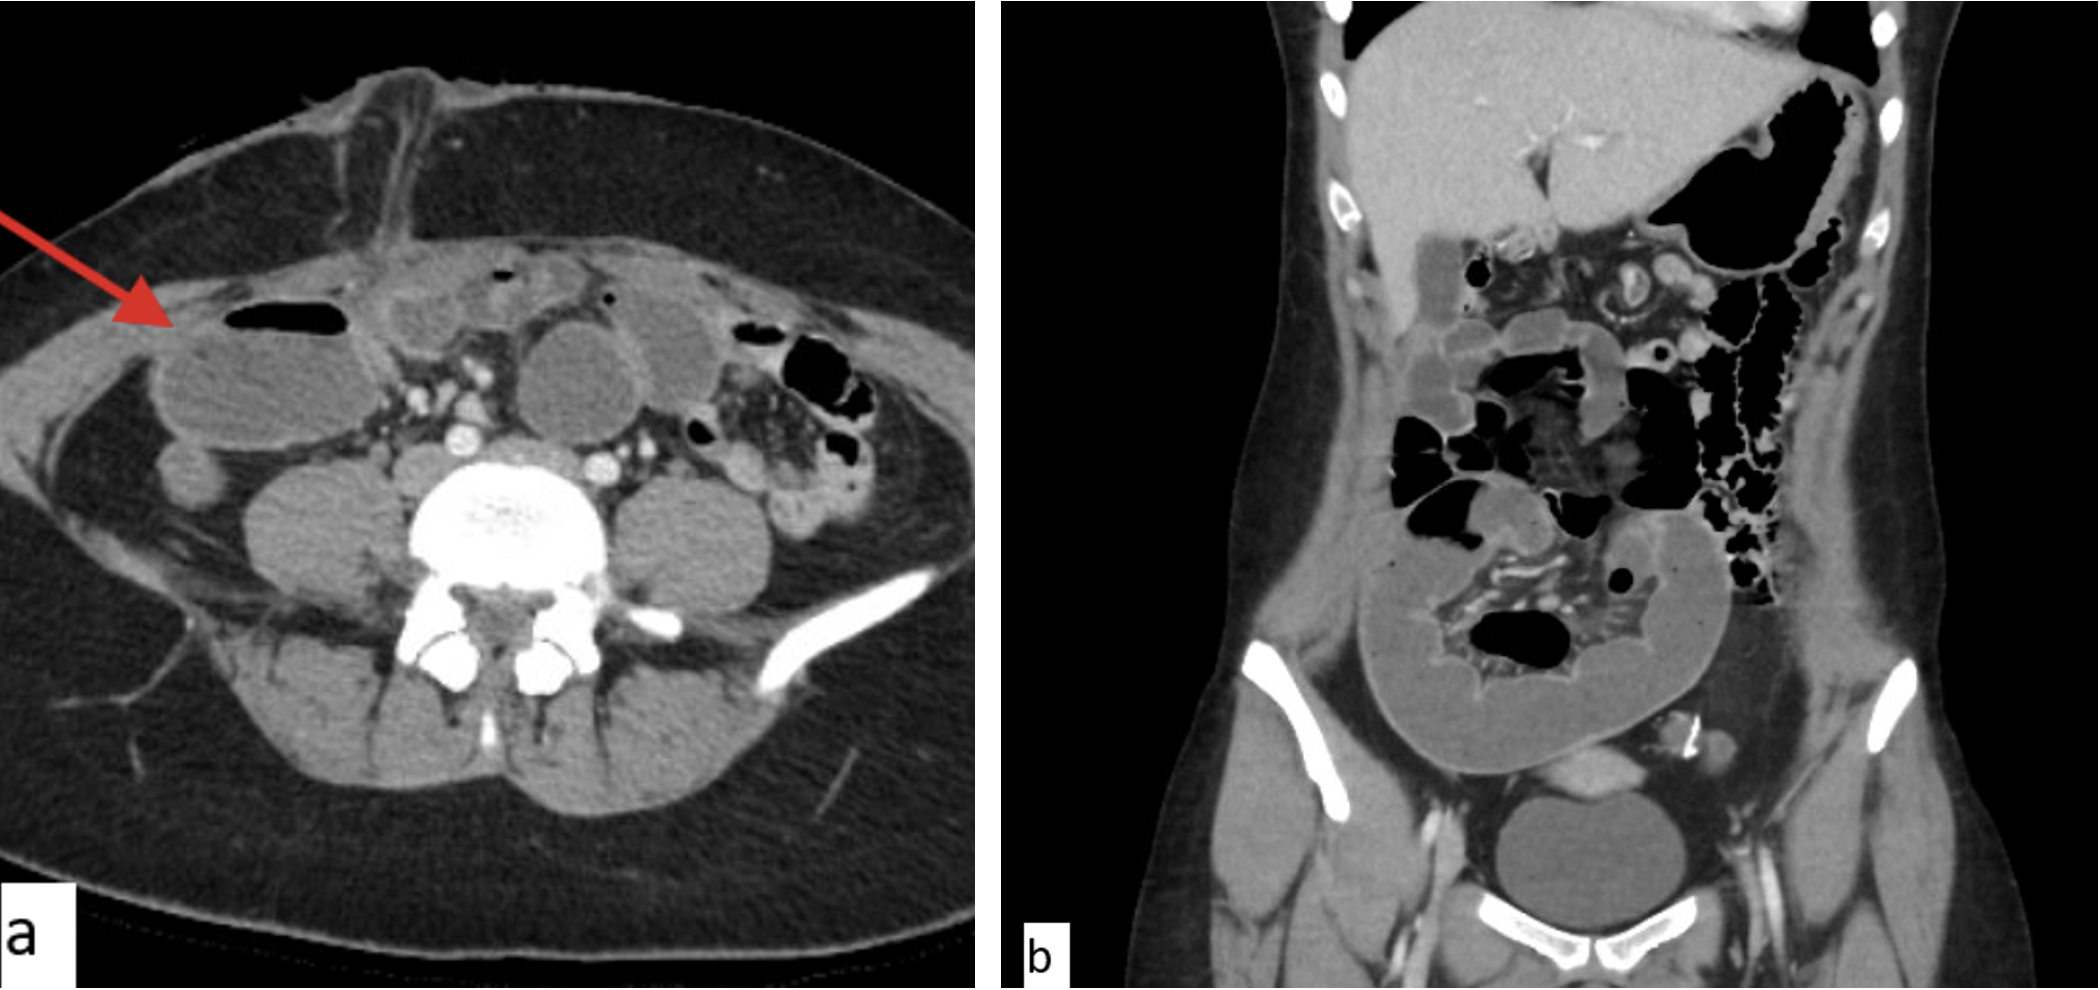

Case Two CT Scans

a) Axial imaging depicting dilated small bowel in the right mid abdomen concerning for obstruction at the level of the ostomy (arrow)

a) Axial imaging depicting dilated small bowel in the right mid abdomen concerning for obstruction at the level of the ostomy (arrow)b) Coronal imaging showing a loop of dilated bowel with decompressed bowel proximally and distally concerning for closed loop obstruction